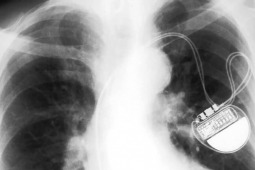

W Polsce każdego roku wzrasta liczba nowych implantacji urządzeń takich jak: stymulatory serca (IPG), kardiowertery-defibrylatory (ICD) oraz stymulatory resynchronizujące (CRT). Największym problemem są komplikacje pojawiające się w okresie odległym po wszczepieniu, często np. po wymianie urządzenia.

Do najważniejszych z nich należą m.in.: infekcje związane z układami, dysfunkcje zastawki trójdzielnej, niedrożność żylna oraz mechaniczne uszkodzenia elektrod. Tu potrzebne jest współne działanie lekarzy rodzinnych i specjalistów tym bardziej, że wzrasta liczba coraz starszych pacjentów

z wszczepionym urządzeniem stymulującym pracę serca.